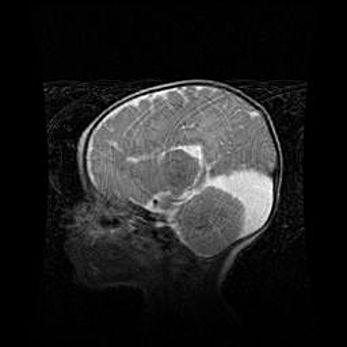

Аномалия Денди-Уокера. Признаки гипоплазии мозолистого тела.

Возраст: 5 месяцев 3 дня

Вес: 5550 г

Пол: мужской

Окружность головы: 39 см

Срок гестации: 40 недель

Аномалия Денди-Уокера – это порок развития головного мозга, для которого характерна триада симптомов: гипотрофия или аплазия червя мозжечка и/или полушарий мозжечка, расширение четвёртого желудочка с формированием ликворной кисты задней черепной ямки, гипертензионная гидроцефалия различной степени.

Гипоплазия мозолистого тела относится к дефектам внутриутробного этапа развития мозговой ткани, возникающим в процессе закладки структур головного мозга, что происходит на начальных этапах развития эмбриона.